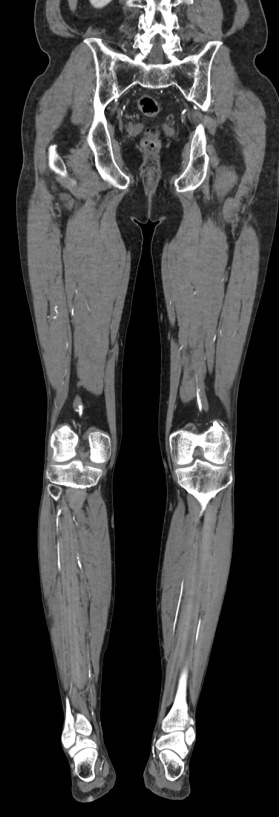

Мультиспиральная компьютерная томография является современным методом обследования сосудистой системы нижних конечностей. Такое исследование по-другому называется КТ-ангиография. Методика позволяет с помощью рентгеновского излучения получить посрезовые снимки и после цифровой обработки создать объемные модели кровеносной системы обеих ног.

В наших медицинских центрах КТ-ангиография нижних конечностей выполняется на современных мультиспиральных компьютерных томографах экспертного уровня TOSHIBA AQUILION. Аппараты послойно сканируют область исследования, одномоментно выполняя множество тончайших срезов. В результате получаются снимки высокого качества и трехмерные модели с изображением даже мелкой сосудистой сети нижних конечностей. При этом методика скоростного мультисрезового сканирования обеспечивает минимальную дозу рентгеновского облучения для пациента.

• КТ сосудов от бифуркации аорты до стопы (данный протокол обследования включает в себя полное обследование сосудов нижних конечностей, включая стопы)